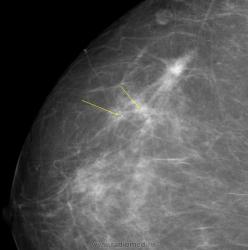

Изображение

Уважаемая Людмила Александровна, а как вы расцениваете участки, отмеченые желтыми стрелками? нет ли здесь мультицентричного рака?

Каюсь, вина моя. Людмила Александровна указала, что имеется "мультифокальный рост".

Сегодня выставлю также её-же аналогичный случай, также инфильтрирующего рака с мультифокальным ростом.